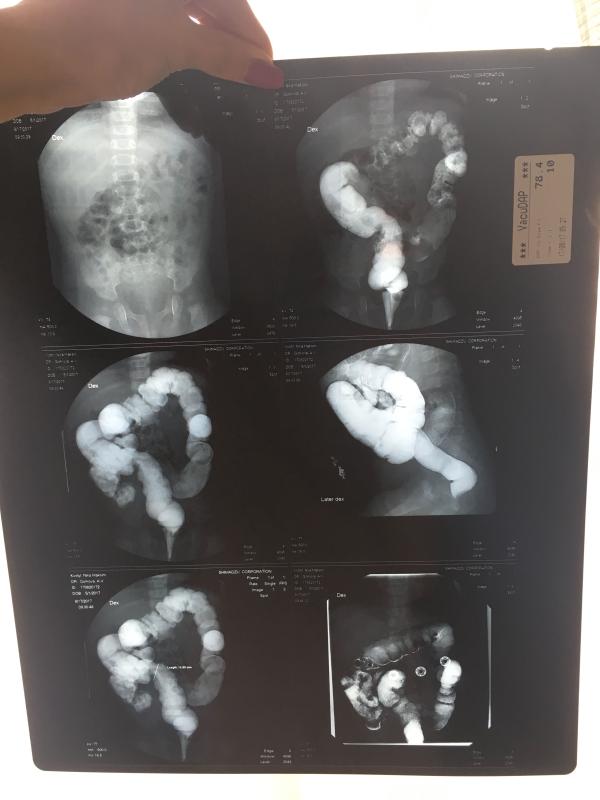

У нас врождённая непроходимость кишечника, ну или врождённая деформация в виде кишечной петли 🤦♀️! Из-за неё ребёнок не может самостоятельно сходить в туалет( и мы с рождения мучаемся с запорами (при этом полностью находимся на Гв)!

Сразу напишу, чтобы многие не писали сюда, что их детки тоже по 5-7 дней не ходили в туалет и на ГВ ЗАПОРЫ ЭТО НОРМА! Это действительно так, в случае, если ребёнка это не беспокоит! Моя же с диким визгом и скрючиванием в букву ЗЮ пыталась тужиться....